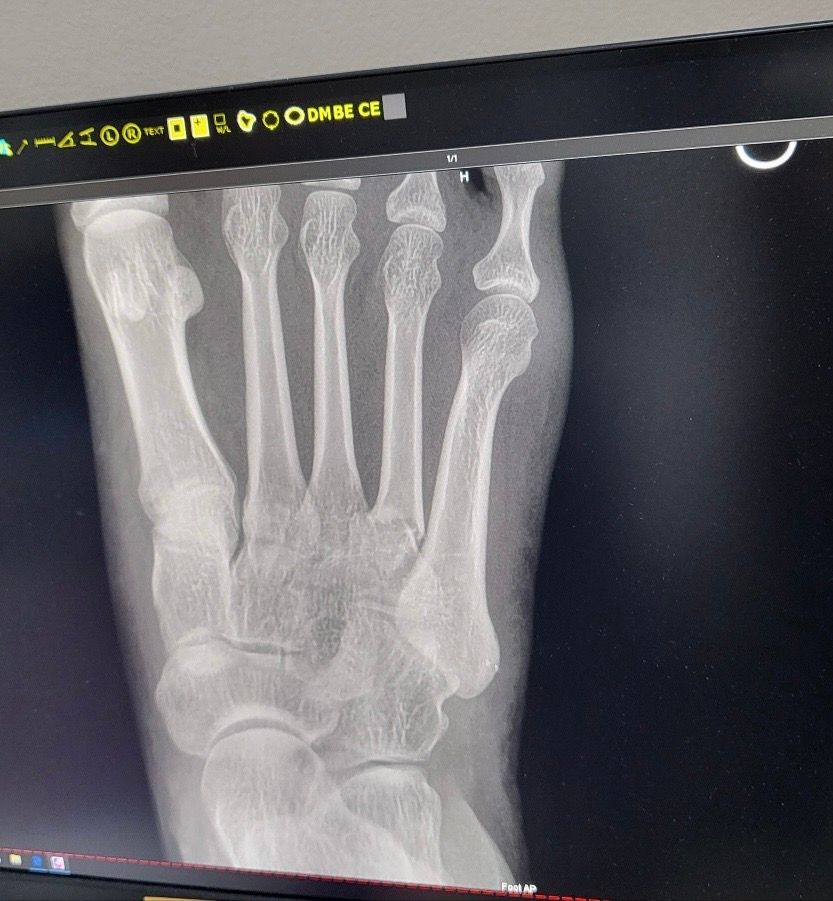

넘어져 발등이 심하게부어서 병원가니 뼈부러짐

어제밤 넘어져 발등이 심하게 멍들고 부어서 근처 한인병원에서 엑스레이를 찍었는데

3,4번 뼈가 부러진것같다고 합니다

4번째 뼈는 어긋난것같아보이는데 심각한가요

• 1번 째 사진